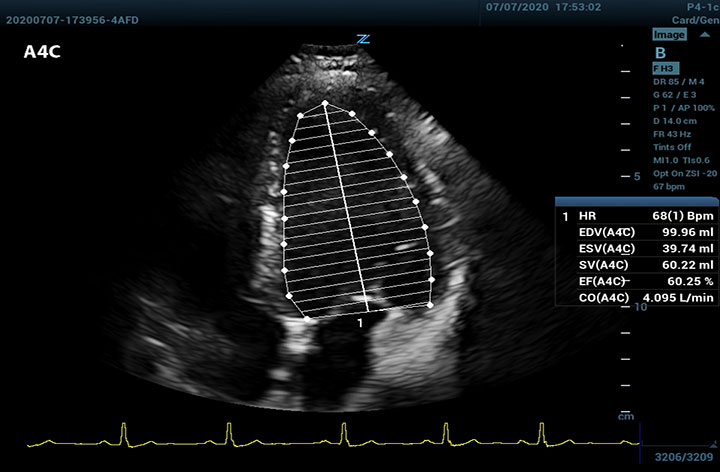

The Z.One PRO Ultrasound System Emerald Edition 2.0 is a powerful and portable advanced point-of-care imaging platform. Powered by software-based ZONE Sonography® Technology+ (ZST+), the Z.One PRO System provides optimal B-mode and Doppler imaging for patients, regardless of body habitus, helping ensure a reliable diagnosis. With a full family of transducers (from 2 – 20 MHz) and a wide range of applications, the Z.One PRO System is the imaging answer to your difficult clinical cases.